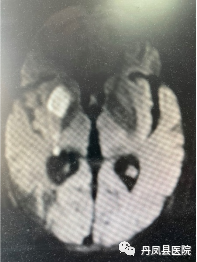

图分别为:溶栓后24小时头颅CT复查无出血;第二天头颅MRI提示右侧基底节区急性脑梗死。